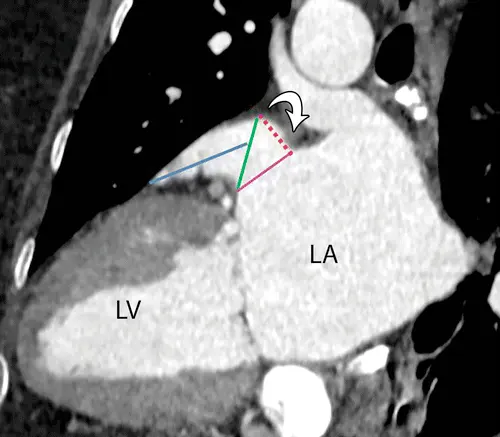

• At CT, the landing zone is identified on the long-axis LAA view. For the Watchman device, the landing zone is located 10–20 mm inside the LAA from the Coumadin ridge (aka limbus). The landing zone diameters for the Watchman device are measured on an en-face-view CT image obtained at a line that connects the LAA adjacent to the left circumflex artery to the point 10–20 mm inward of the Coumadin ridge. 1

• Caption: Vertical long-axis-view CT image of the left ventricle (LV) shows how the landing zone for a Watchman device is identified at a distance of 10–20 mm (red dotted line) distal to the Coumadin ridge (arrow). The pink line is the LAA ostium. The landing zone diameter is measured in the plane between this point and the point where the left circumflex artery is located (green line). The length of the LAA is also measured on the same image from the landing zone to the tip of the dominant lobe (blue line).